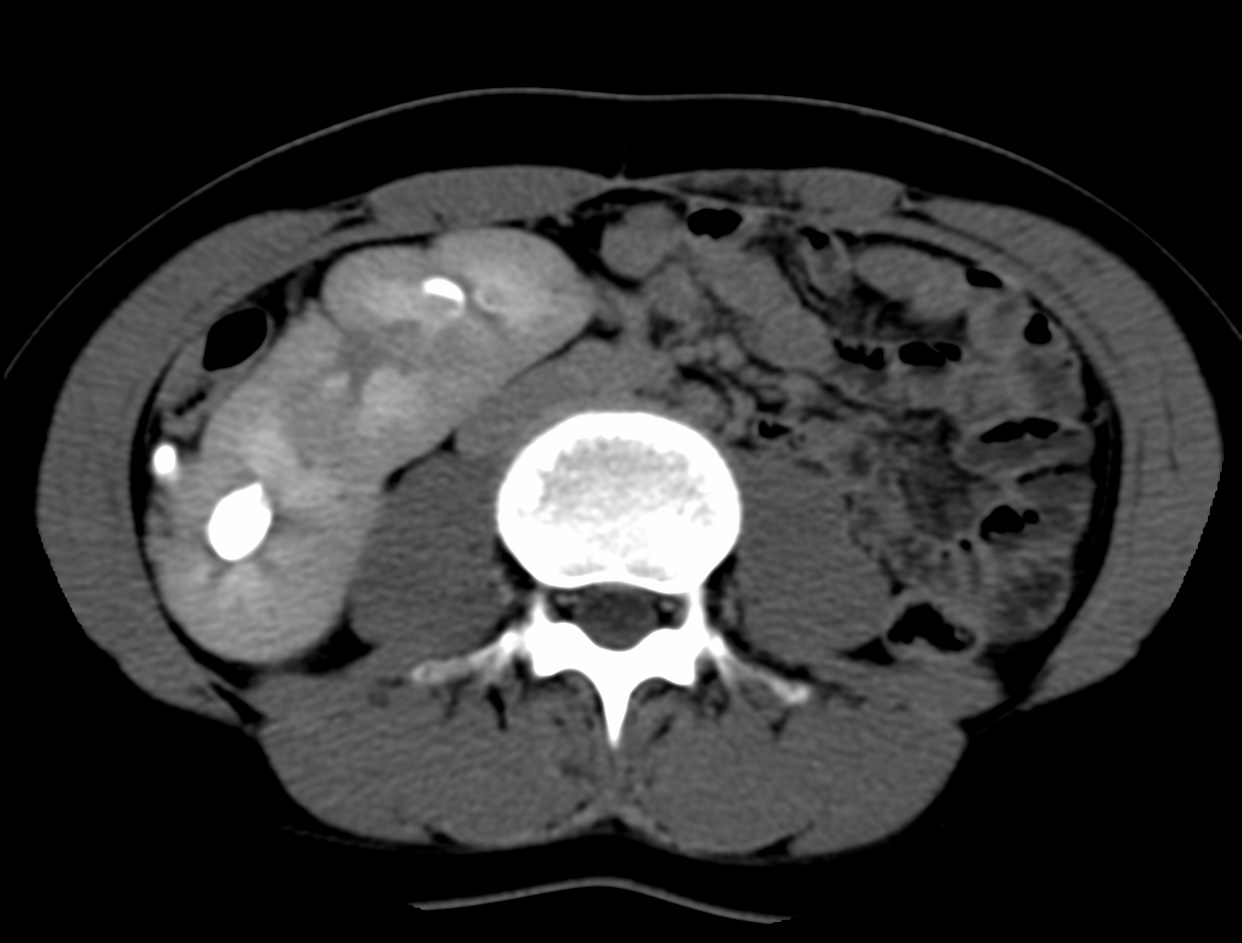

Caso #1: Ectopía Renal Cruzada Fusionada

Paciente femenina en la que se identificó ausencia de riñón izquierdo en fosa renal, con fusión renal en flanco derecho. Las reconstrucciones 3D y cortes axiales confirman una ectopía renal cruzada tipo A con malrotación de ambos riñones. Cada uréter conserva su trayecto anatómico hacia su meato correspondiente en vejiga.

Corte axial TC Reconstrucción 3D 1 Reconstrucción 3D 2 Plano sagital VR uréteres